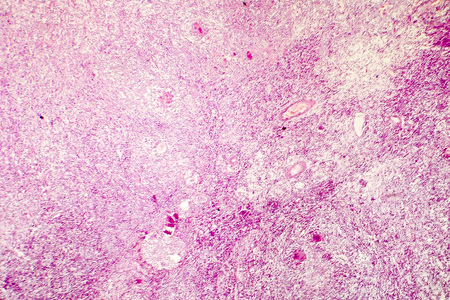

- Description: Photo by drmicrobe. Liquefactive necrosis of the human brain, light photomicrograph showing loss of cell outlines, accumulation of cellular debris, macrophage infiltration. Developes in stroke, necrotising encephalitis

abscess bacteria brain cavity cells central nervous system cns colliquative necrosis cyst edema encephalitis eosin fungi gliosis hematoxylin histology histopathology human light microscope light microscopy liquefaction liquefactive necrosis macrophages micrograph necrotising neural neurology neuron neuronal photomicrograph proliferating glial cells stained stroke tissue